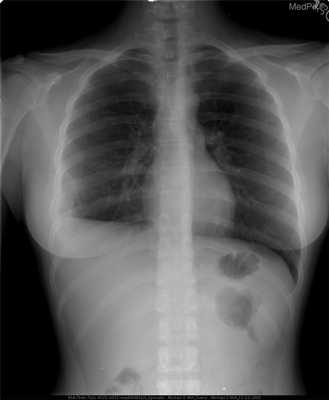

Наиболее часто поражаются кости черепа, бедренные кости, реже — кости таза, ребра, позвонки. Известны также случаи появления патологических очагов в тимусе, коже, мочевом пузыре, паращитовидных железах, гипоталамусе, легких и желудочно-кишечном тракте.

Использование различных методов визуализации (рентгенография, КТ, МРТ) позволяет выявить очаги деструкции величиной до 5 см с четкими границами без склеротических изменений, иногда — патологические переломы, уплощение пораженных позвонков (vertebra plana).